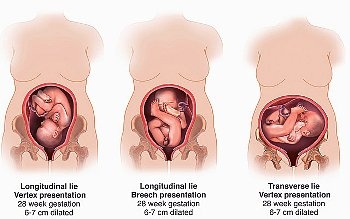

положення плода - Це відношення його поздовжньої осі, яка проходить через його потилицю і таз до поздовжньої осі матки.

■ Поздовжнє - Довгі осі матки і плода збігаються,

■ Поперечний - Поздовжні осі дитини і матки перпендикулярні один одному,

■ Косе - Поздовжні осі малюка і матки утворюють гострий кут, тобто це положення є середнім між першими двома.

Поздовжнє положення відноситься до норми і зустрічається в переважній кількості вагітностей. Косе і поперечне положення вважаються патологією і створюють непереборні перешкоди для природних пологів.

Передлежання плоду визначається частиною тіла, якої він спрямований до входу в родові шляхи. У медицині її називають предлежащей частиною. Передлежання плоду може бути головним - коли малюк розташований головкою вниз, тазові - коли біля входу в шийку матки лежать сідниці дитини, або поперечним - коли малюк лежить поперек до входу в родові шляхи і передлежачої частина тіла не визначається.

Головне передлежання плода

Тазове або сідничне передлежання плода